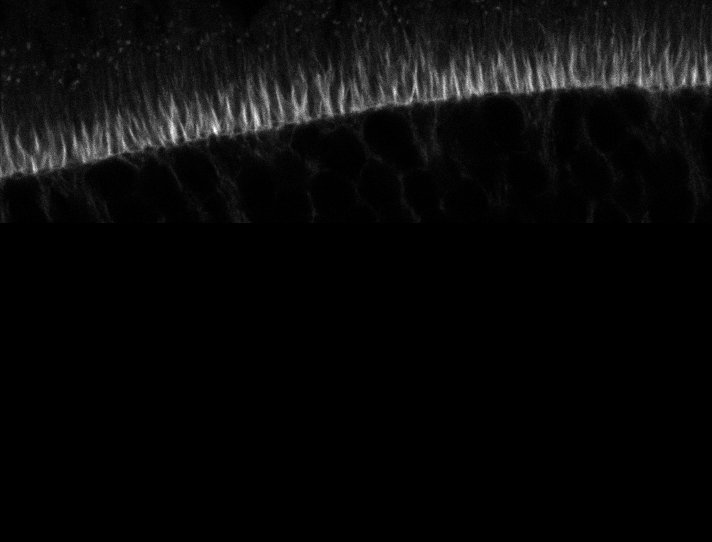

Healthy Retina

Unhealthy Retina

Healthy Eye